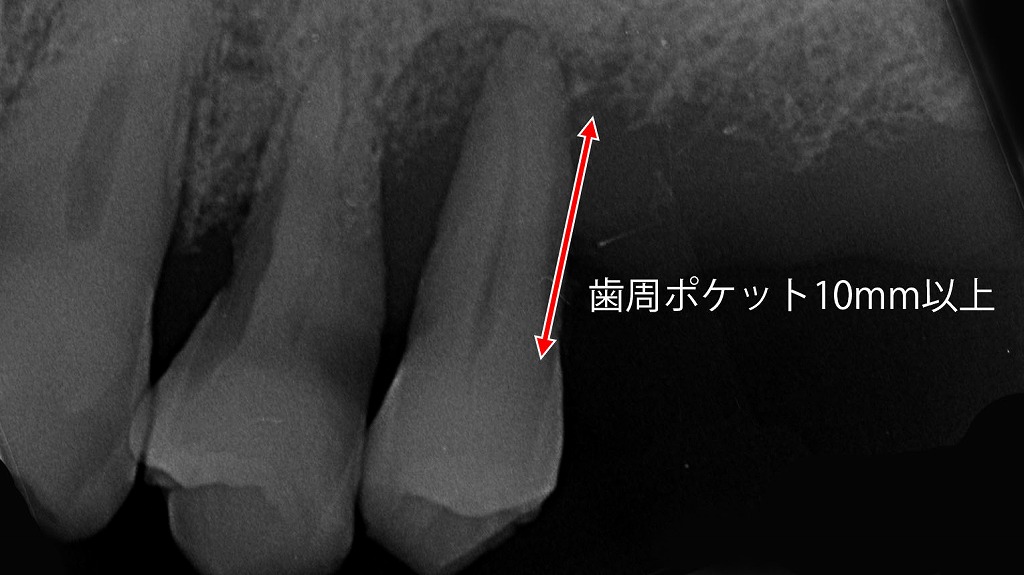

🖼️ 同症例のレントゲン写真での確認

- レントゲン上で第2小臼歯から第1大臼歯にかけて骨の著しい吸収を確認

- 骨が溶けた部分は黒く写る

- 第2小臼歯では歯根膜腔の拡大も認められ、動揺度は2度(横に1〜2mm動く)